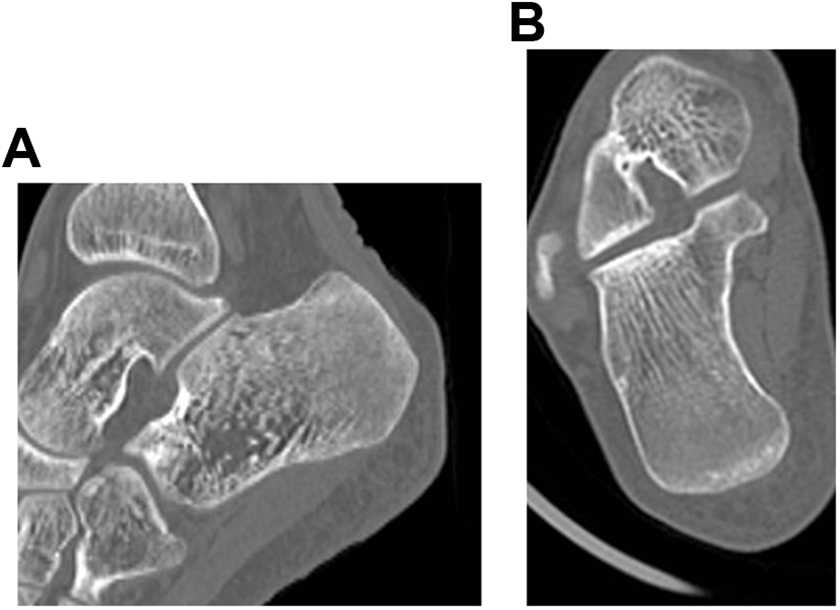

Hematological tests showed pancytopenia (Table 1). X-ray and computed tomography (CT) showed no evidence of destruction of the trabeculae in the left calcaneus (Figure 1 and Figure 2A,B). However, on MRI, the middle to posterior part of the left calcaneus showed low intensity in T1-weighted image, high intensity in T2-weighted image, and high intensity in short-TI inversion recovery (Figure 3A-C). Taking all clinical physical findings into consideration, we suspected that the lesion of the left calcaneus was either a lymphoproliferative tumor, such as leukemia, multiple myeloma, or lymphoma, or a trabecular type bone metastatic tumor, such as small cell carcinoma.

Sagittal (A) and coronal (B) computed tomography images showing no trabecular bone destruction.